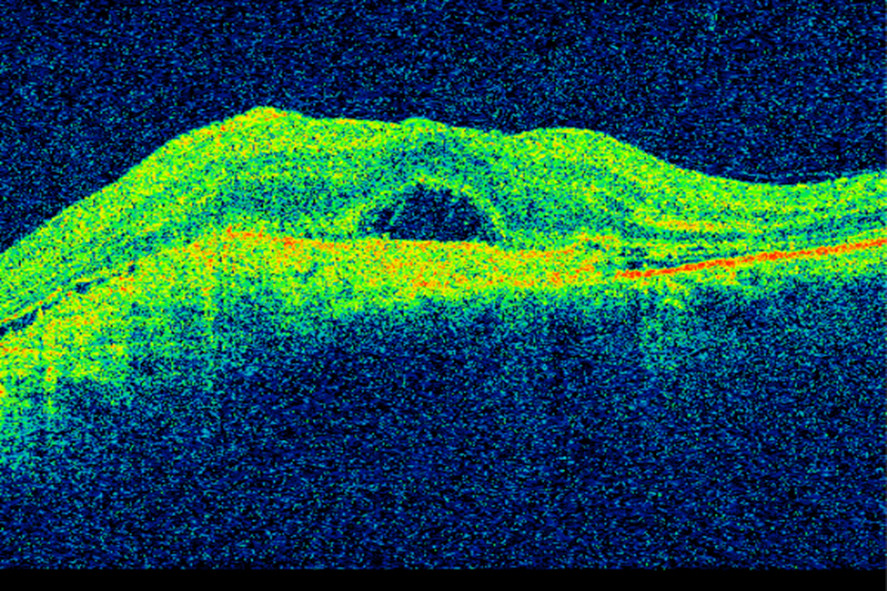

Samtidig som bevacizumab ble tatt i bruk på kreftpasienter, ble VEGF-hemmeren pegaptanib (Macugen) godkjent i USA for behandling av våt aldersrelatert makuladegenerasjon (3). Pegaptanib nøytraliserer VEGF165, som er en av de fire isoformene av vaskulær endotelial vekstfaktor. Pegaptanib fikk raskt konkurranse. Kort tid etter at bevacizumab ble godkjent for kolorektal kreft, ble det gitt til pasienter med våt makuladegenerasjon. En liten studie viste klar bedring av visus, redusert netthinnetykkelse og mindre lekkasje fra neovaskulære forandringer etter bevacizumab gitt intravenøst (13). Amerikanske øyeleger begynte deretter å injisere medikamentet intravitrealt (direkte i øyets glasslegeme) (14). Norske øyeavdelinger var tidlig ute med å tilby denne behandlingen. Intravitreale injeksjoner med VEGF-hemmere er meget effektivt i behandlingen av våt aldersrelatert makuladegenerasjon og andre øyesykdommer, og innebærer lav risiko for komplikasjoner og bivirkninger (15, 16). I denne sammenhengen må det nevnes at utviklingen av optisk koherens-tomografi (optical coherence tomography, OCT) i øyefaget har hatt stor klinisk, vitenskapelig og økonomisk betydning. Optisk koherens-tomografi er en hurtig og ikke-invasiv undersøkelsesmetode som ved hjelp av lysbølger avbilder øyets anatomiske strukturer med mikrometer-oppløsning (17) (figur 1). Teknologien anvendes i dag innen de fleste av øyefagets underspesialiteter, men især ved diagnostisering og oppfølging av øyesykdommer som rammer netthinnen og den utenforliggende årehinnen. Figur 2 og 3 viser OCT-bilder av makula med våt aldersrelatert makuladegenerasjon i samme pasient før og etter oppstart med anti-VEGF-behandling.

Figur 2 OCT av makula hos pasient med våt aldersrelatert makuladegenerasjon før oppstart med anti-VEGF-behandling. Det ses…

Figur 2 OCT av makula hos pasient med våt aldersrelatert makuladegenerasjon før oppstart med anti-VEGF-behandling. Det ses blant annet fortykket netthinne og subretinal væske. Visus er 0,1.